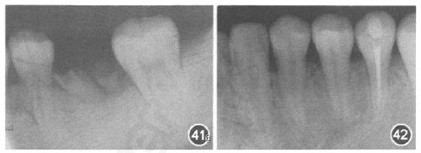

移植牙牙周情况正常、无异常松动度、无根尖症状,咀嚼功能良好。x线片显示,上前牙回收显著,移植牙牙周膜问隙正常,硬骨板形成,无根尖病变。(摘自《中华口腔医学杂志》)